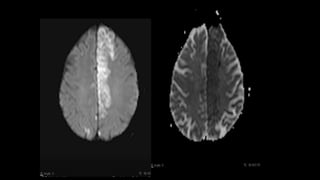

• #126 Pvs tends to be sharpely marginated , ovoid and linear with complete suppression on flair however lacunar infarcts are often irregular with FLAIR hyperintense rim.